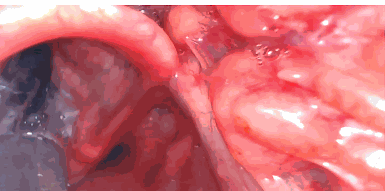

2- introducimos muy profundo y aquí lo vemos en esta imagen (1) que inclusive se ve en la parte inferior el esófago y yo veo aquí las los cartílagos aritenoides y que si yo introduzco el tubo en esa forma pues irremediablemente me voy a ir a el esófago. Pero lo puedo corregir y una de las formas de corregirlo es liberar un poquito esa imagen retirar un poco y redirigir el tubo y con esta maniobra pues tenemos mucho

más éxito.

3-Choque con aritenoides Cuando yo quiero introducir el tubo y choca muy frecuente con el cartílago aritenoides éste es por lo mismo porque a lo mejor la introducción es muy profunda porque el tubo no lo monte bien en una guía o porque simplemente con el hecho de retirarse un poquito de redirigirte es la forma en la que vas a poder realizar y tener un éxito en tu intubación